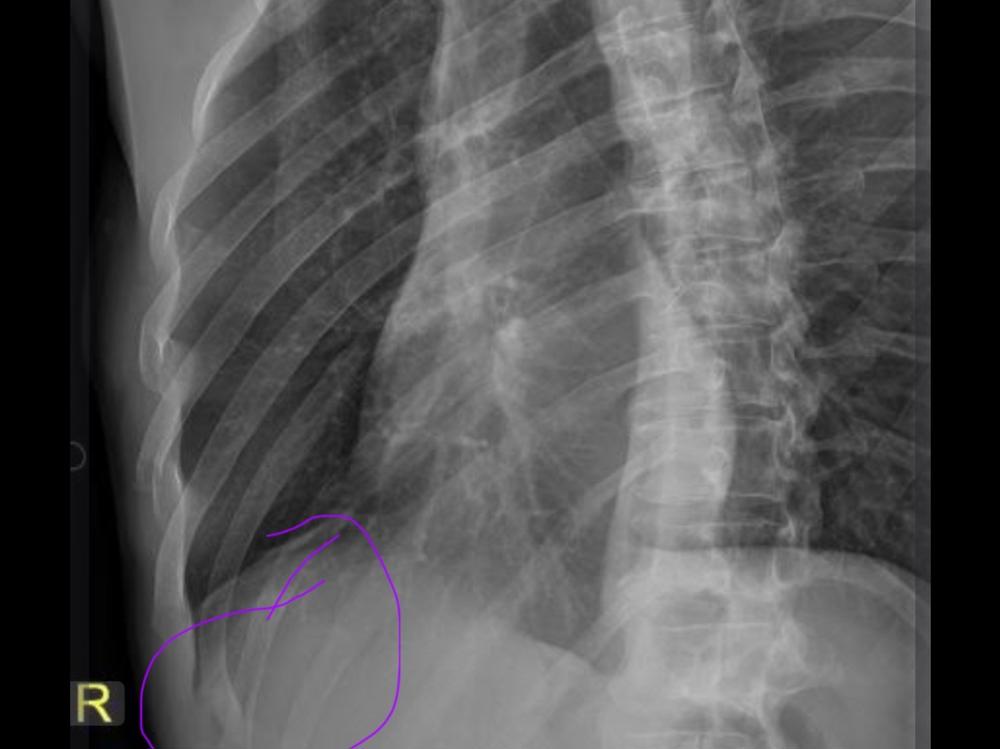

I have had my own fair share of medical issues including a chronic lung condition lung surgery , two days ago I tripped over my fur baby

And I’ve broke my ribs leaving me bedridden and in a huge amount of pain unable to do my normal household and work duties.